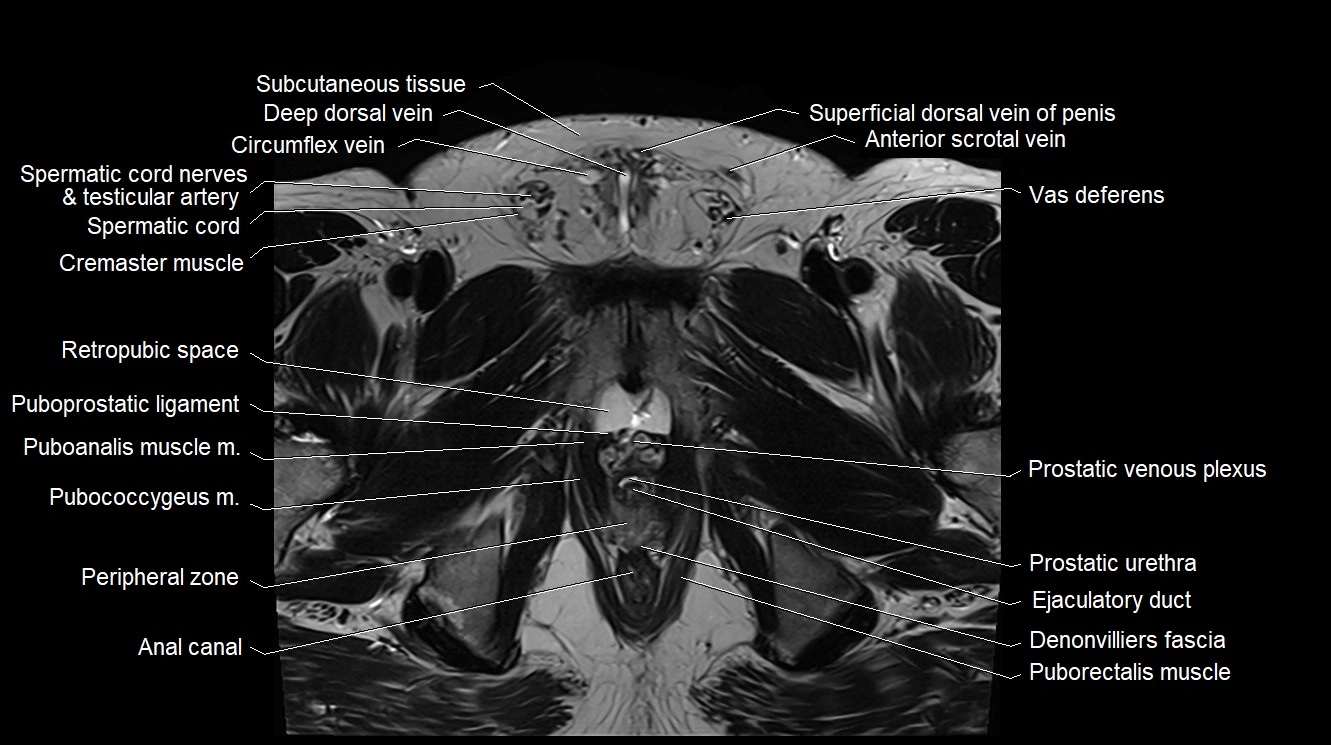

- Anal canal

- Cremaster muscle

- Ejaculatory duct

- Peripheral zone of prostate

- Prostatic urethra

- Puboanalis muscle

- Pubococcygeus muscle

- Puboprostatic ligament

- Puborectalis muscle

- Rectoprostatic fascia (Denonvilliers' fascia)

- Retropubic space

- Sacral lymph nodes

- Spermatic cord

- Spermatic cord nerves

- Subcutaneous tissue (scrotum)

- Superficial dorsal vein of penis

- Vas deferens